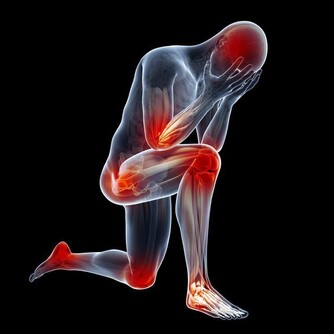

3、突然出現一過性半身麻木乏力,以手足部位最為突出。

這些症狀是頸內動脈系統短暫腦缺血發作所致,從而影響了偏側肢體活動的感覺和運動功能。

4、在意識清醒的情況下,雙腿突然發軟,甚至跌倒,

但爬起來後步態又如常,這也常是腦幹缺血的表現。